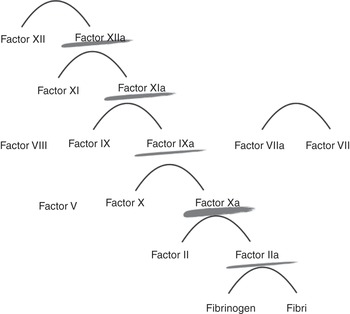

Heparin acts at various levels of the coagulation cascade, as shown in Figure 7.1.